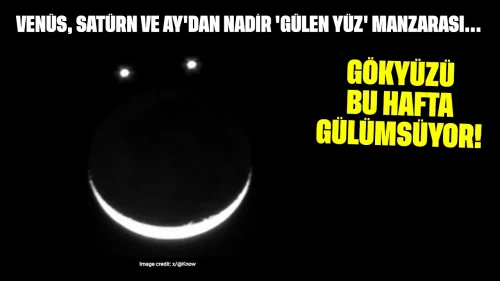

Kolon kanseri, kalın bağırsakta gelişen ve genellikle ileri yaş gruplarında teşhis edilen bir kanser türü olarak biliniyor. Ancak yeni veriler, genç yaşlarda da vakaların arttığını gösteriyor. Özellikle Batı tarzı beslenme, hareketsiz yaşam tarzı, obezite, aşırı şeker tüketimi ve çevresel faktörlerin bu artışa neden olduğu belirtiliyor.

Vakalar Artıyor Gençler de Risk Altında

Kolon Kanserini Tetikleyen Risk Faktörleri

Gençlerde Kolon Kanseri İçin Erken Teşhis Neden Önemli?